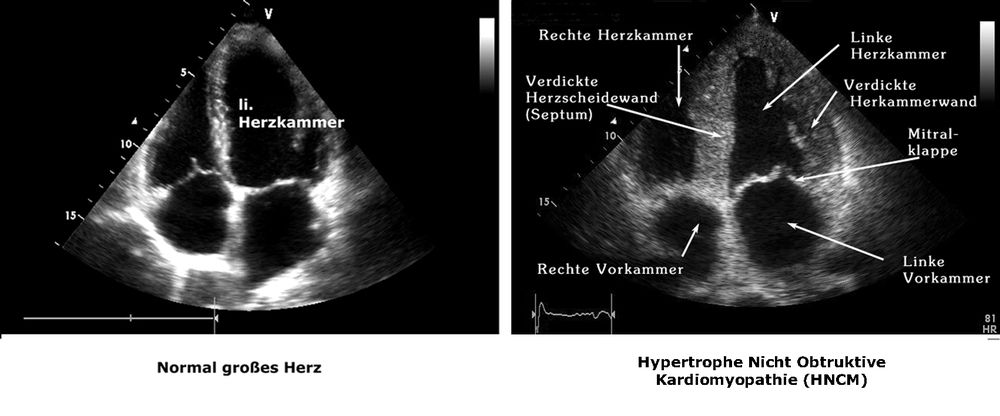

Bei bekannten Risikofakturen sind zur Früherkennung einer asymptomatischen koronaren Herzerkrankung und Risikoevaluation bestimmte Untersuchungen sinnvoll. Hierzu zählen in erster Linie das Belastungs-EKG und das Langzeit-EKG, aber auch eine Ultraschalluntersuchung des Herzens.